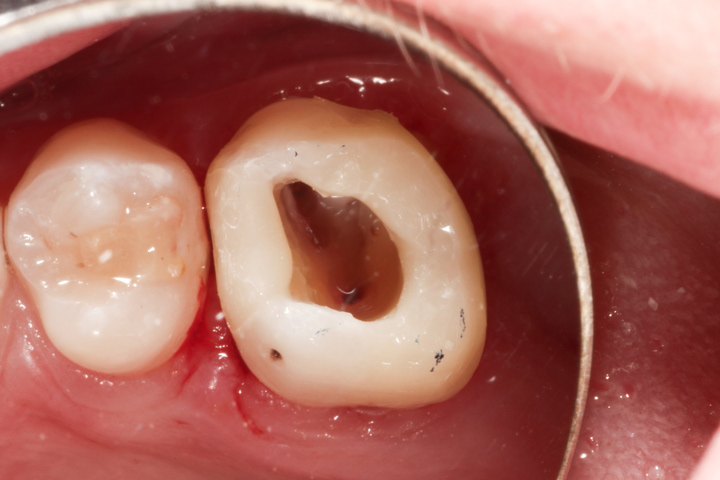

PRZYKŁAD 2